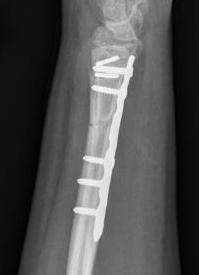

Operative management

1. Anatomical ORIF of distal radius with dynamic compression plate

- anatomical reduction

- restoration of radial bow

- compression for healing

Radius ORIF with dynamic compression plates